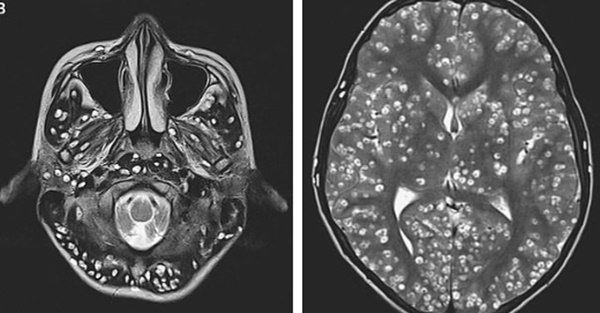

Kết quả chụp cộng hưởng từ xác nhận, bệnh nhân bị rất nhiều nang ở vùng vỏ não. Tổn thương cũng xuất hiện ở vùng cuống não – là gốc của cơ quan cực kỳ quan trọng này, nơi gửi tín hiệu từ não tới các phần còn lại của cơ thể. Nang còn được phát hiện ở tiểu não.

Kết quả chụp MRI cho thấy người đàn ông có nhiều u nang trong vỏ não (hình bên trái là các chấm trắng). Các tổn thương cũng được tìm thấy trong thân não và tiểu não (nhìn bên phải).